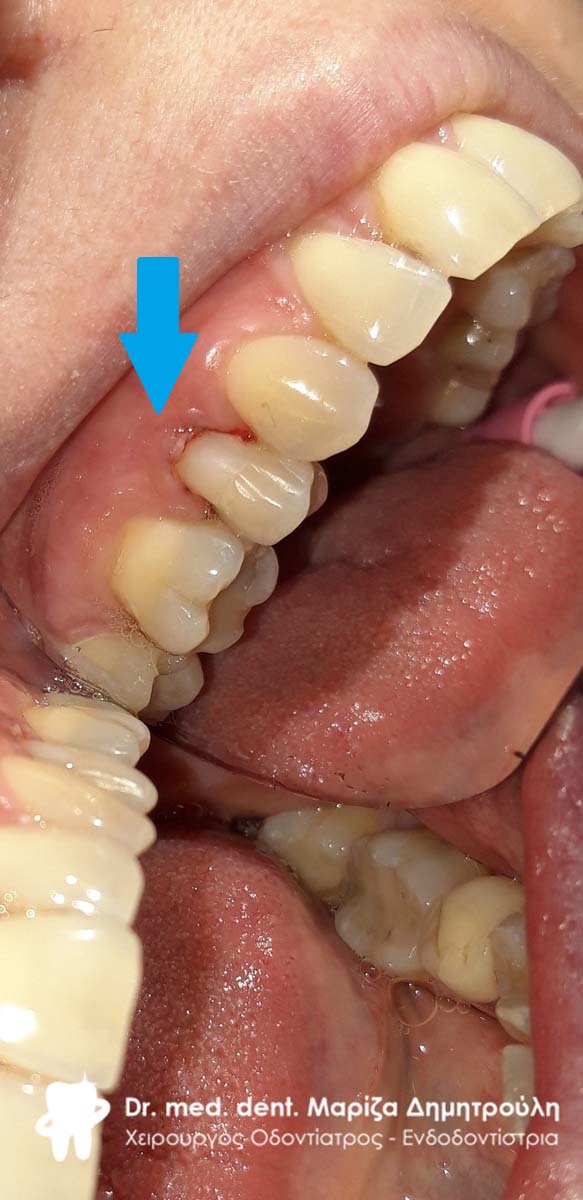

Περιστατικό – Αυχενικό σφράγισμα δοντιού

Σκοπός της ασθενούς ήταν τόσο η αισθητική όσο και η λειτουργική (η αθενής είχε ευαισθησία στα ψυχρά ροφήματα και τροφές) αποκατάσταση των αυχενικών αλλοίωσεων στους κάτω δεξιούς προγομφίους. Η αποκατάσταση πραγματοποιήθηκε με λευκά σφραγίσματα σύνθετης ρητίνης.

ΠΡΙΝ

META